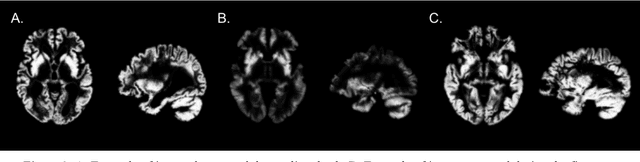

The use of neural networks for diagnosis classification is becoming more and more prevalent in the medical imaging community. However, deep learning method outputs remain hard to explain. Another difficulty is to choose among the large number of techniques developed to analyze how networks learn, as all present different limitations. In this paper, we extended the framework of Fong and Vedaldi [IEEE International Conference on Computer Vision (ICCV), 2017] to visualize the training of convolutional neural networks (CNNs) on 3D quantitative neuroimaging data. Our application focuses on the detection of Alzheimer's disease with gray matter probability maps extracted from structural MRI. We first assessed the robustness of the visualization method by studying the coherence of the longitudinal patterns and regions identified by the network. We then studied the stability of the CNN training by computing visualization-based similarity indexes between different re-runs of the CNN. We demonstrated that the areas identified by the CNN were consistent with what is known of Alzheimer's disease and that the visualization approach extract coherent longitudinal patterns. We also showed that the CNN training is not stable and that the areas identified mainly depend on the initialization and the training process. This issue may exist in many other medical studies using deep learning methods on datasets in which the number of samples is too small and the data dimension is high. This means that it may not be possible to rely on deep learning to detect stable regions of interest in this field yet.